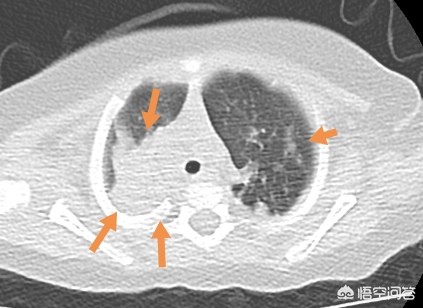

像这位小朋友,重症支原体肺炎,由于粘稠的分泌物堵塞气道,炎症吸收很缓慢,后来通过支气管镜灌洗,清理了气道的毒素和分泌物。

当天下午孩子的精神状态就恢复很多,咳嗽明显减轻,也喜欢吃奶了,睡觉也安稳了。